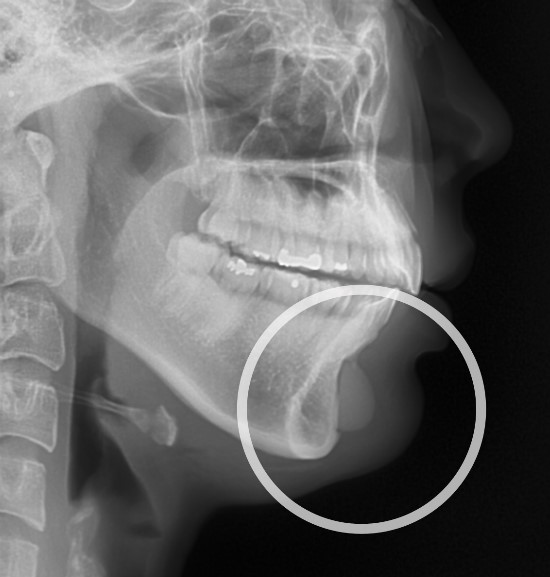

무턱인경우 절골수술 또는 보형물을 통해 앞턱을 볼록하게 만들어 줄 수 있습니다. 허나 잘못된 위치에 보형물이 자리잡거나 절골이 잘못될 경우 앞턱이 부자연스럽고 턱의 모양이 어색하게 보이는 증상이 생깁니다. 아래는 보형물이 잇몸바로 아래에 위치하고 있어 턱의 모양이 브이라인이 되지 못하고 이중턱으로 보여지는 사례입니다.

앞턱보형물의 잘못된 위치

현재 엑스레이에서 보여지는 보형물의 위치보다 6~7mm 아래로 이동될 경우 이상적인 볼륨을 기대할 수 있습니다.사례는 긴곡선절제술과 앞턱보형물재수술이 적용되었습니다.